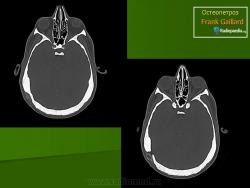

Лабораторная и инструментальная диагностика. Характерны гипокальциемия, гипофосфатемия и повышение уровня ПТГ в сыворотке (вторичный гиперпаратиреоз). Всасывание кальция в кишечнике усилено, но гипокальциемия тем не менее сохраняется, поскольку ПТГ не активирует остеокласты. При рентгенографии и денситометрии костей обнаруживают их равномерное уплотнение и увеличение костной массы; компактное и губчатое вещество имеют одинаковую плотность. При гистологическом исследовании биоптатов кости выявляются толстые прослойки неминерализованного органического матрикса, иногда встречаются признаки остеомаляции (рахита). Количество остеокластов нормальное или даже увеличенное, но они малоактивны.